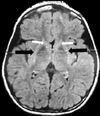

Westphal variant Huntington’s Disease

- aka Juvenile onset Huntington’s

- < 5% of cases

- Presents with hypokinetic movement features often described as parkinsonian, unlike the hyperkinetic features of adult HD

- Hypokinetic: Bradykinesia, rigidity

- Hyperkinetic: Dystonia, myoclonus, seizures

- Imaging: (MRI or CT)

- Bilateral atrophy of the head of the caudate nucleus and putamen